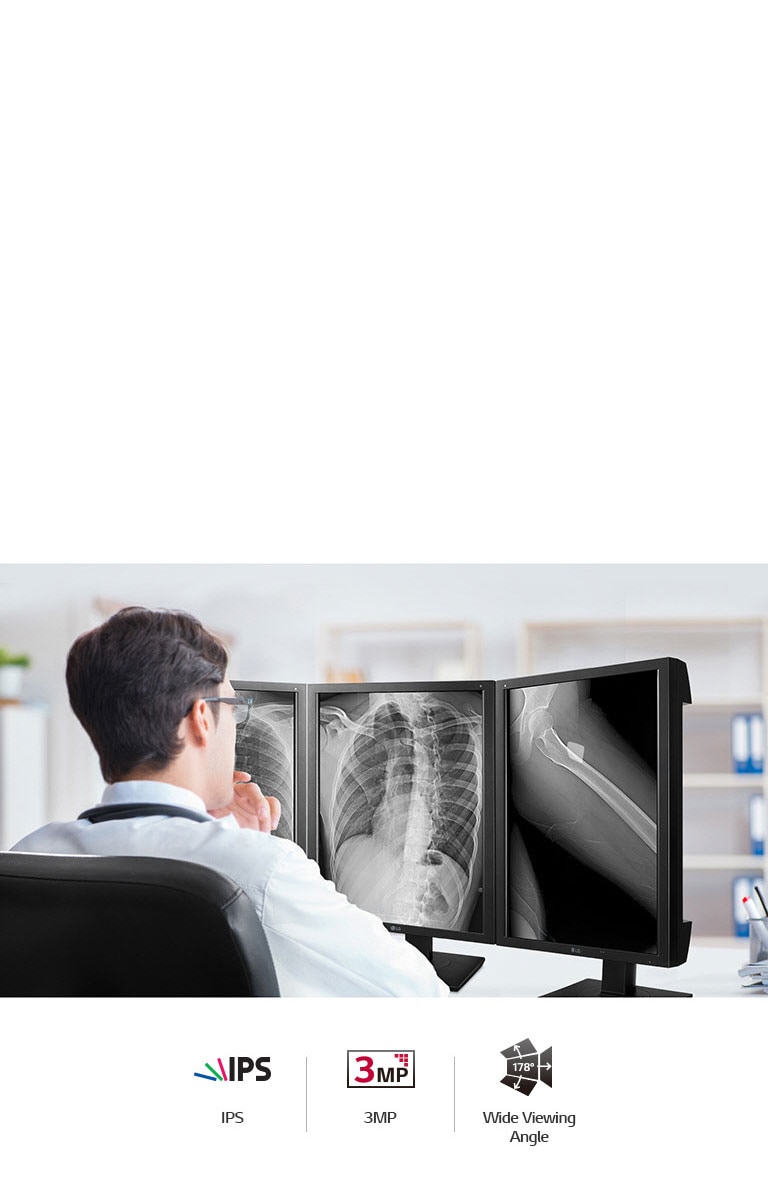

21.3” High Brightness (2048 x 1536) 3MP Color IPS Diagnostic Monitor

Reliable Image for Diagnosis

*Image for illustration purpose only.